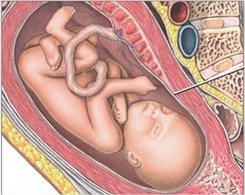

Com 22 semanas de gestação o bebê já possui unhas e brinca com as mãozinhas, passando pelo rosto e orelhas. Agora o desenvolvimento fetal dele já está completo e mostra um bebê perfeito, apenas um pouco mais magro que o dia do nascimento. Se a mamãe não consegue mais comer como antes tem que tentar fazer refeições menores, mas nunca ficar mais de 3 horas sem se alimentar. Seu bebê precisa crescer! Agora ele pesa cerca de 430 gramas e mede algo em torno de 27 cm.

Os ossos do ouvido já se formaram totalmente1 e sua audição está em adaptação, porém consegue escutar com grande nitidez as vozes do lado de fora. Como ainda tem muito espaço na barriga, o bebê se movimenta tranquilamente, dá piruetas e brinca com pernas e mãos do jeito que deseja. É melhor aproveitar, pois logo esse espaço dentro do útero irá acabar. Os traços do seu bebê, como nariz e boca, estão definidos e podem ser vistos através do exame de ultrassonografia.

Seus ossos, cartilagens e músculos começam a ficar cada dia mais firmes e fortes2. Os pequenos chutes e cotoveladas já são intensamente sentidos pela mamãe. Daqui a pouco essa sensação poderá ser compartilhada com o papai, que ao colocar a mão sentirá os movimentos do seu herdeiro ou princesa.